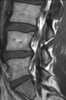

Pars interarticularis defect

Spondylolysis (spon-dee-low-lye-sis) is defined as a defect or stress fracture in the pars interarticularis of the vertebral arch. The vast majority of cases occur in the lower lumbar vertebrae (L5), but spondylolysis may also occur in the cervical vertebrae. [Source: Wikipedia ]